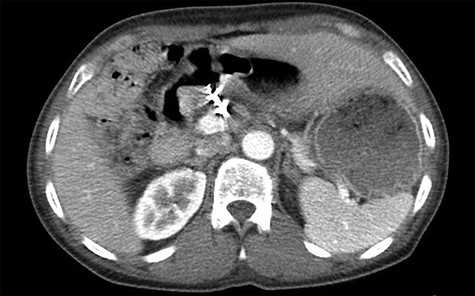

Single axial view of subsequent computed tomography scan demonstrating scattering from GDA coil with associated area suspicious for ulcer in duodenal bulb

Three years later, the patient presented to the emergency department with epigastric pain as well as melena. The patient could not remember the last time he took any acid suppression medication. He had increased his intake of ibuprofen. The patient was found to have a Hgb of 6.5 g/dl. He was given 2 U of PRBC and was taken to the endoscopy suite by the gastroenterology team. The endoscopy demonstrated a posterior duodenal bulb ulcer with a metallic ring in the center (Fig. 3). At this point, the general surgery team was consulted. A computed tomography scan of his abdomen and pelvis was obtained to further guide our operative decision-making (Fig. 4).